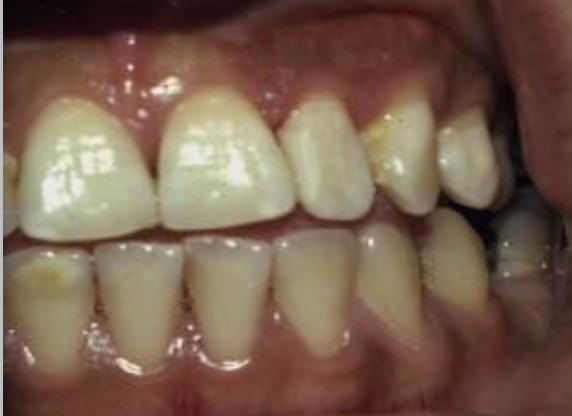

Q

How would describe this image?

A

gross coronal decay